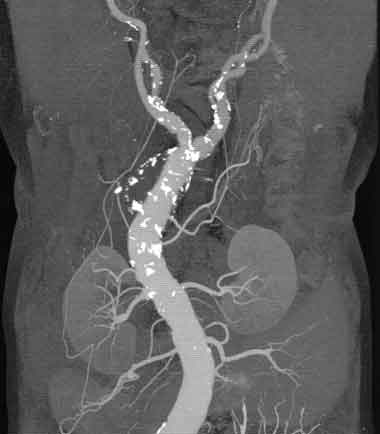

В частности магистральные сосуды туловища и конечностей, а также сосудов шеи и головного мозга. Метод исследования нетравматичен для пациента.

Все вышеизложенные методы диагностики проводятся с помощью Мультисрезового спирального компьютерного томографа Toshiba (Asteion Super 4) - 26 декабря 2006 года выпуска, который находится на базе 19-й городской больницы.

Аппарат Toshiba Astieon Super 4: относится к системе 3 поколения с непрерывным оборотом трубки и наиболее подходит для исследования головного мозга и всего тела включая исследования сердечно – сосудистой системы. Многосрезовая технология системы Asteion позволяет получать действительно изотропные объёмные данные. Эта технология позволяет расширить применение КТ и значительно увеличивает диапазон исследований.